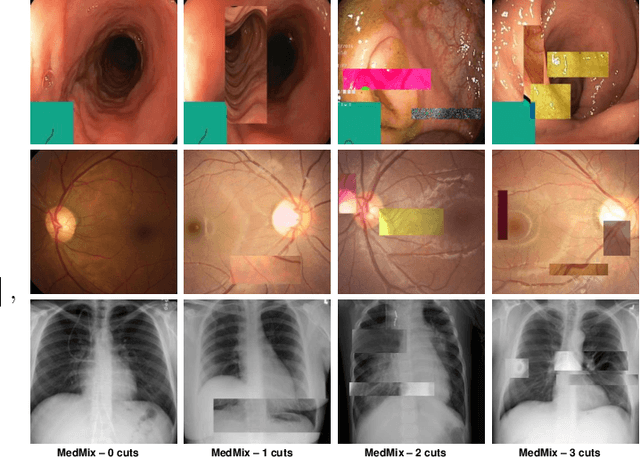

Abstract:The scarcity of high quality medical image annotations hinders the implementation of accurate clinical applications for detecting and segmenting abnormal lesions. To mitigate this issue, the scientific community is working on the development of unsupervised anomaly detection (UAD) systems that learn from a training set containing only normal (i.e., healthy) images, where abnormal samples (i.e., unhealthy) are detected and segmented based on how much they deviate from the learned distribution of normal samples. One significant challenge faced by UAD methods is how to learn effective low-dimensional image representations that are sensitive enough to detect and segment abnormal lesions of varying size, appearance and shape. To address this challenge, we propose a novel self-supervised UAD pre-training algorithm, named Multi-centred Strong Augmentation via Contrastive Learning (MSACL). MSACL learns representations by separating several types of strong and weak augmentations of normal image samples, where the weak augmentations represent normal images and strong augmentations denote synthetic abnormal images. To produce such strong augmentations, we introduce MedMix, a novel data augmentation strategy that creates new training images with realistic looking lesions (i.e., anomalies) in normal images. The pre-trained representations from MSACL are generic and can be used to improve the efficacy of different types of off-the-shelf state-of-the-art (SOTA) UAD models. Comprehensive experimental results show that the use of MSACL largely improves these SOTA UAD models on four medical imaging datasets from diverse organs, namely colonoscopy, fundus screening and covid-19 chest-ray datasets.